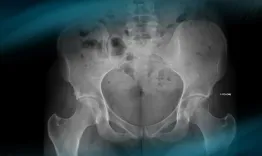

Follow the making of a custom acetabular component, from the patient X-ray to the surgery. In this webinar, leading experts share invaluable insights and groundbreaking techniques!

Custom implants for acetabular reconstruction

Nicolas Reina, James Donaldson, Marco Schiraldi